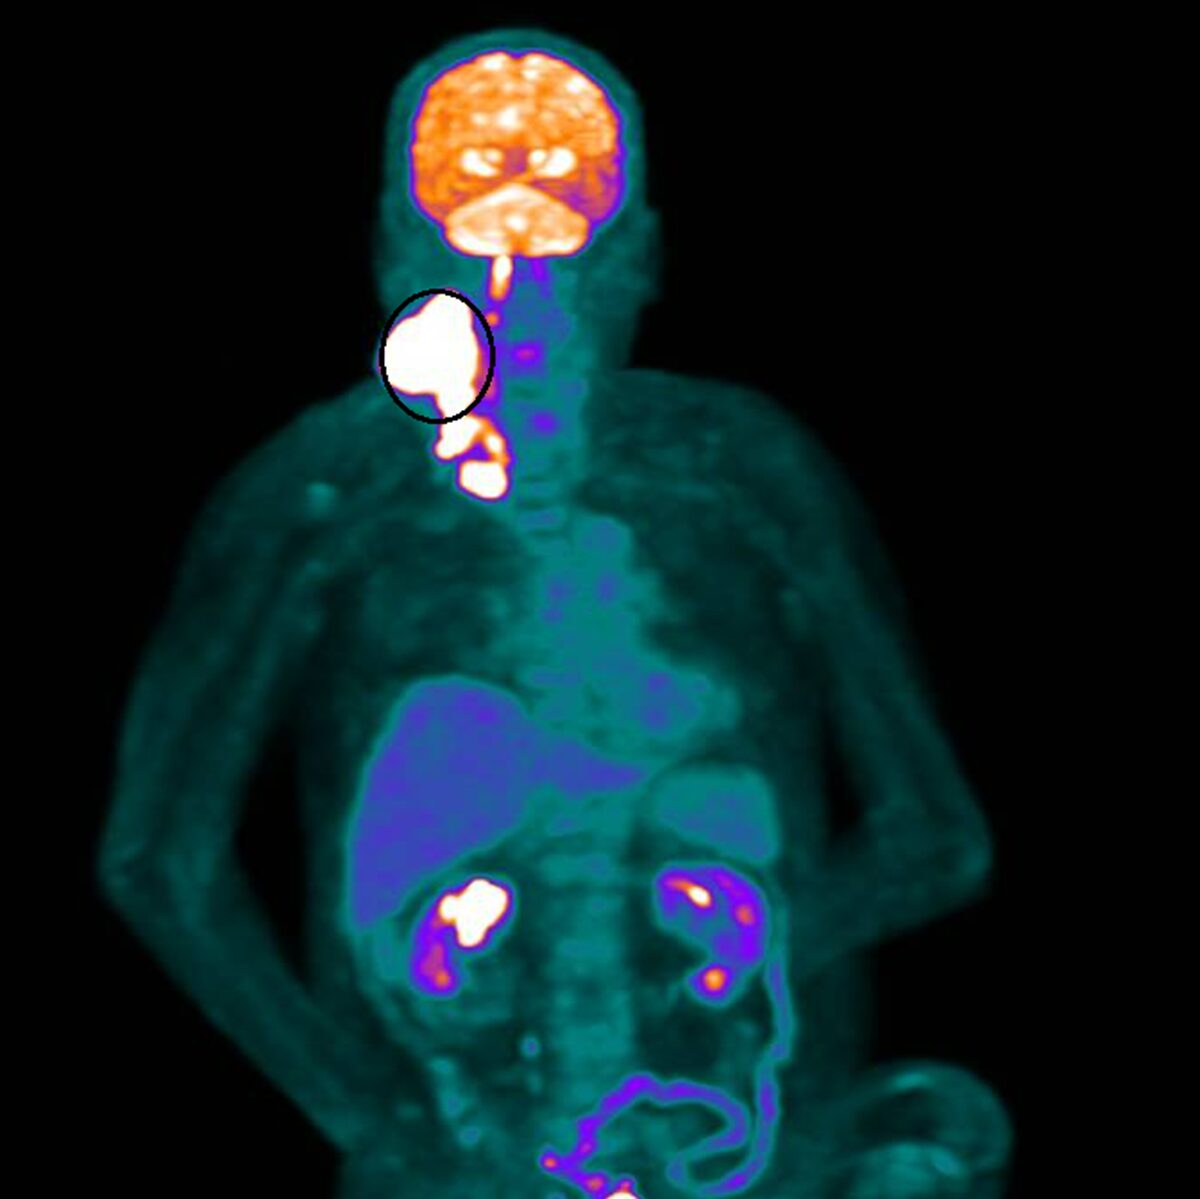

認證制度,為癌友打造康復之路